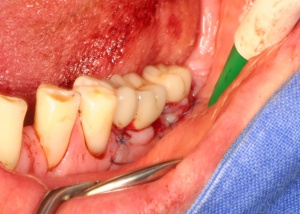

In der präimplantologisch chirurgischen Phase ist darauf zu achten, dass möglichst viel Knochen bei einer Osteotomie erhalten bleibt. Die labiale/bukkale Knochenlamelle genießt besonderen Schutz. Häufig macht es Sinn, den Zeitpunkt einer Extraktion bzw. einer Osteotomie sowie deren Technik mit dem implantierenden Kollegen abzustimmen oder diese auch durch den Implanteur selbst vornehmen zu lassen (Abb. 4).

Eine weichgewebschirurgische Vorbereitung des zukünftigen Implantatlagers bereits zu diesem Zeitpunkt ist häufig ratsam. Dazu gehört unter anderem wie in diesem Bildbeispiel die Verbreiterung der Zone keratinisierter Gingiva. Eine gedeckte Einheilung des Implantates wird somit wahrscheinlicher. Therapeutisch kompliziertere Eingriffe nach der Freilegung oder sogar erst nach prothetischer Versorgung werden vermieden (Abb. 5a/b).